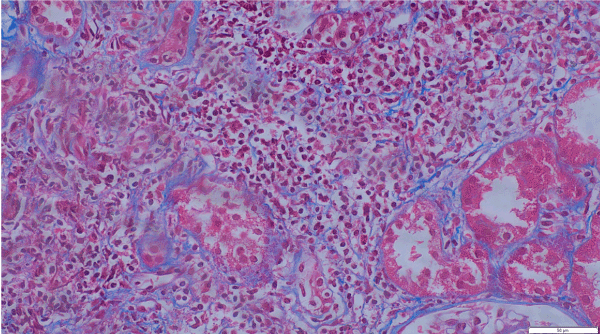

Polyomavirus and Cytomegalovirus PCR were below detectable levels. A graft kidney biopsy was performed. The biopsy showed a moderate interstitial inflammation rich in eosinophils and there was no evidence of rejection, as shown in Figure 1.

Figure 1. Masson trichrome stain; x400 interstitial inflammation rich in eosinophils

In acute allergic drug-induced interstitial nephritis, the major histologic abnormalities are in the interstitium which is expanded by a number of inflammatory cells with the presence of large numbers of eosinophils, as is seen in this patient [7,10,15,18,19]. The true incidence of AZA causing TIN is not very well known. Hence, with any transplant patient who has been started on AZA and develops graft dysfunction, one needs to keep TIN as a differential diagnosis [20-24].